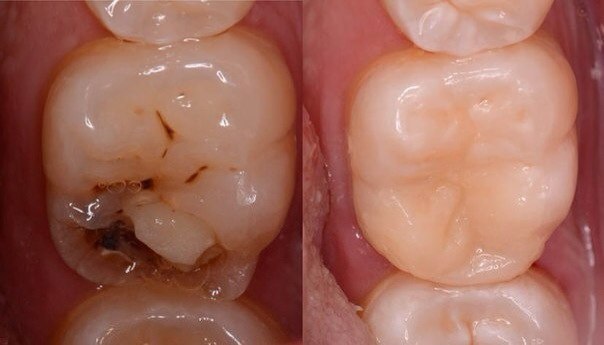

Лечение зубов под микроскопом: фото до и после

Лечение под микроскопом – это возможность для врача осуществлять постоянный контроль хода лечения, оно избавляет пациента от необходимости проходить промежуточное рентгеновское обследование. Иногда весь процесс лечения требует применения увеличительной техники. Благодаря этому врач может с минимальными повреждениями раскрыть полости, грамотно их обработать, промыть, запломбировать. Использование микроскопа и других современных технологий не являются альтернативой профессионализму врачей.